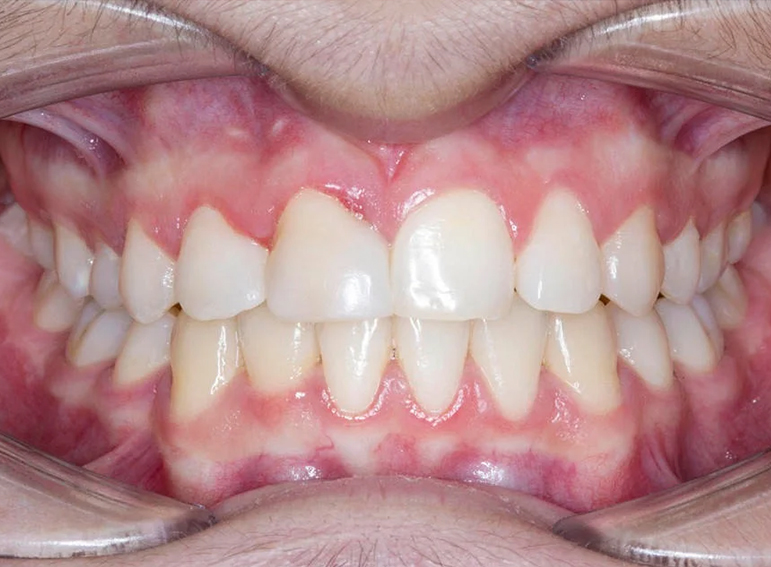

Composite restoration of an UR3 to resemble an UR1 following orthodontic treatment.